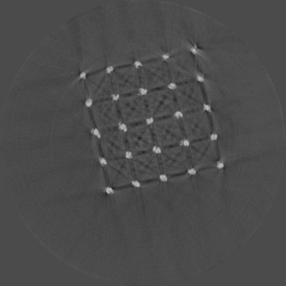

Using the Ti scaffold sample, a post reconstruction analysis between Si detector (Medipix3.1) operating in Single Pixel Mode (SPM) and CdTe detector (Medipix3RX) operating in CSM was carried out. Figure 6a shows a reconstruction for energy range 30 to 50 keV obtained using Si detector with a detector element size 55 m in SPM. Despite good spatial resolution, artefacts are still prominent. The reconstruction using CdTe detector with a detector element size of 110 m in CSM (figure 6b) shows reduced artefacts comparatively. To obtain the narrow energy range of 35 to 55 keV, the raw counts at 35 to 80 keV and 55 to 80 keV were subtracted.